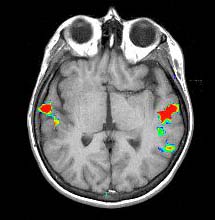

| Activación |

La activación del hemisferio izquierdo es claramente mayor. La activación se encuentra en las siguientes áreas: Área de Broca (imagen 5), área de Wernicke (imágenes 4 y 5), circunvolución supramarginal izquierda (área de asociación heteromodal, imagen 5), corteza motora y premotora izquierda. Las áreas auditivas primarias también están activadas, predominantemente en el lado izquierdo. |